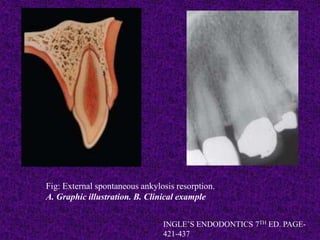

Fig: External spontaneous ankylosis resorption.

A. Graphic illustration. B. Clinical example

INGLE’S ENDODONTICS 7TH ED. PAGE-

421-437